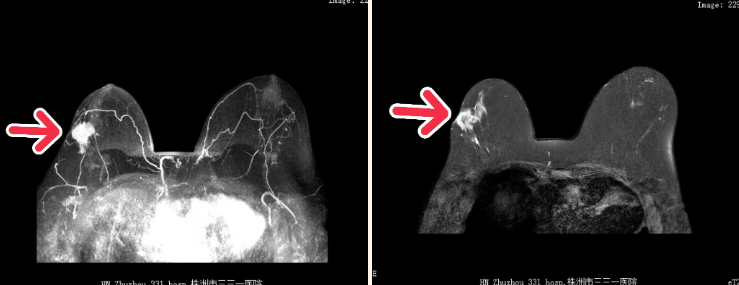

通过乳腺磁共振动态对比剂增强成像,能清晰捕捉乳腺组织的血流动力学变化。可帮助对乳腺病变进行定位定性,为乳腺癌早诊早治奠定基础。

在乳腺癌术前分期中,乳腺磁共振增强可精准界定病灶大小、边界,明确肿瘤是否侵犯胸肌筋膜、皮肤或乳头,同时清晰显示腋窝淋巴结转移情况。对外科手术有指导意义,为手术方案(如保乳手术、根治术)制定提供可靠依据。